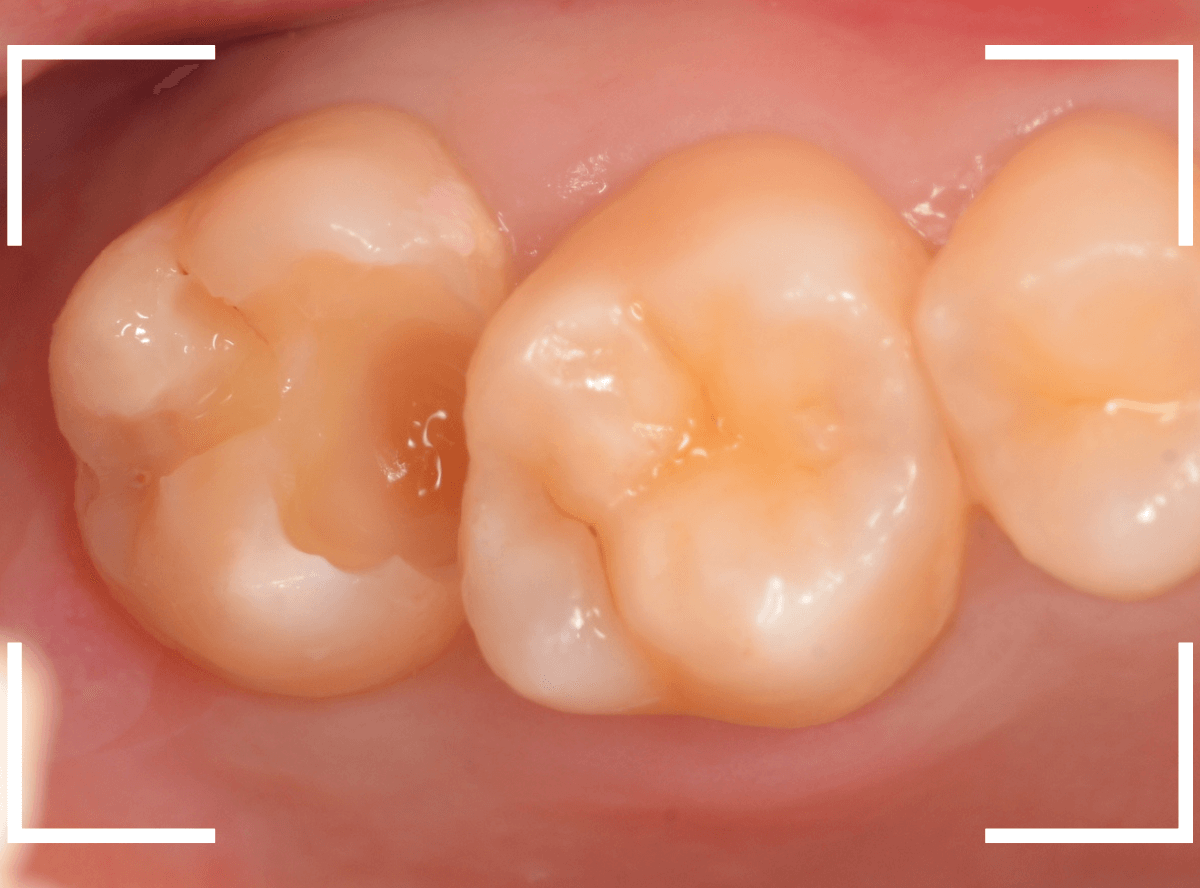

全ての虫歯を除去しました。

レントゲン写真からある程度確認出来ましたが、歯の神経スレスレまで虫歯が進行していました。

ここまで虫歯が進行していても、全く症状を感じない事も多いです。

そして、ある時急に痛みを感じるのです。